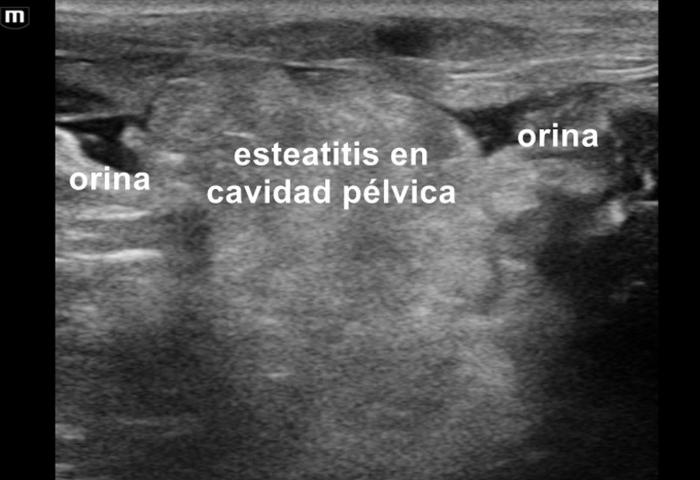

Mediante el estudio ultrasonográfico se detectó la presencia de líquido acumulado en la cavidad pélvica, en la zona peri-uretral, con esteatitis asociada (Figura 5). Debido a estos hallazgos se sospechó una ruptura traumática de la uretra, por lo cual se sometió a la paciente a una prueba de contraste uretral positivo, la cual evidenció la perforación uretral (Figura 6).